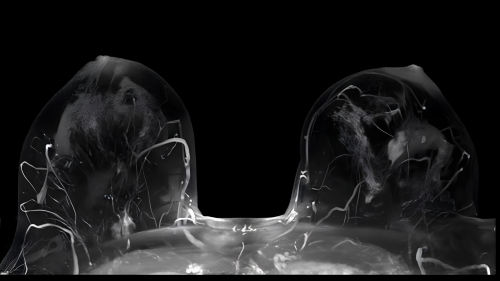

3.6. Các kỹ thuật hình ảnh khác

Trong trường hợp ung thư vú đã được chẩn đoán, các thăm dò hình ảnh bổ sung có thể được chỉ định để đánh giá khả năng di căn xa, thường bao gồm chụp cắt lớp vi tính (CT scan) hoặc chụp cộng hưởng từ (MRI scan).

Hình 3: Hình ảnh khối u vú trái trên MRI